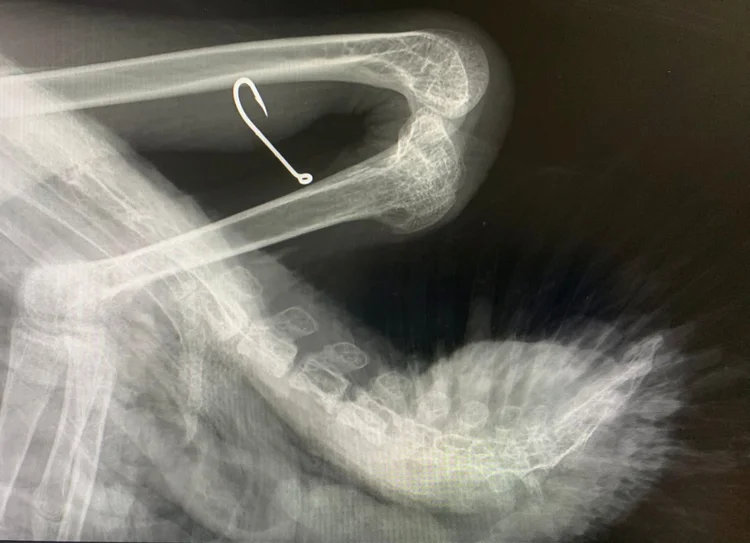

Nå er høstsesongen i gang, og dette er høysesong for svaner i nød. Svaneungene skal snart ut på vingene for aller første gang, og da skjer det dessverre ofte ulykker som krever vår hjelp. I tillegg må vi stadig rykke ut for å fjerne fiskeutstyr og annen forsøpling som setter seg fast på fuglene.

Vi er en frivillig organisasjon som dekker alle utgifter selv – blant annet veterinærkostnader, fôr, husholdningsutstyr, medisiner, medisinsk utstyr og drift av utrykningskjøretøyet vårt. Den siste tiden har vi hentet flere knoppsvaner som måtte fraktes til dyreklinikk for akutt behandling, og vi har nå flere fakturaer som må betales. Les gjerne om disse på vår facebookprofil.